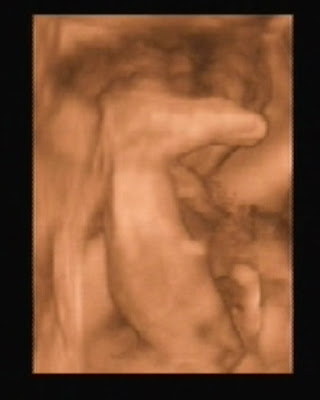

Ecografía 4D

Holaaaaa, buen día!!!!! Llegó el momento de mostrarle mi cara al mundo!

Esta mañana mis papis fueron para verme en 4D. los acompañó mi abu Cris. Lo mejor de todo, es que estoy super bien, todos los parámetros normales, un poco grandote, pero super sanito!

Casi que no me dejo ver porque estaba muy cómodo boca abajo, como mirando la columna de mi mamá, por eso en el momento en que les mostré mi carita, aprovecharon para sacarme muchas fotos!!!

Ya peso 1,216 kg.

Todos dicen que en esta foto me parezco mucho a mi hermana mayor! Será verdad?

Cochinín!!! chupando la placenta... puaj!

Dándole duro a mi mami... acá adentro, todavía mando yo!